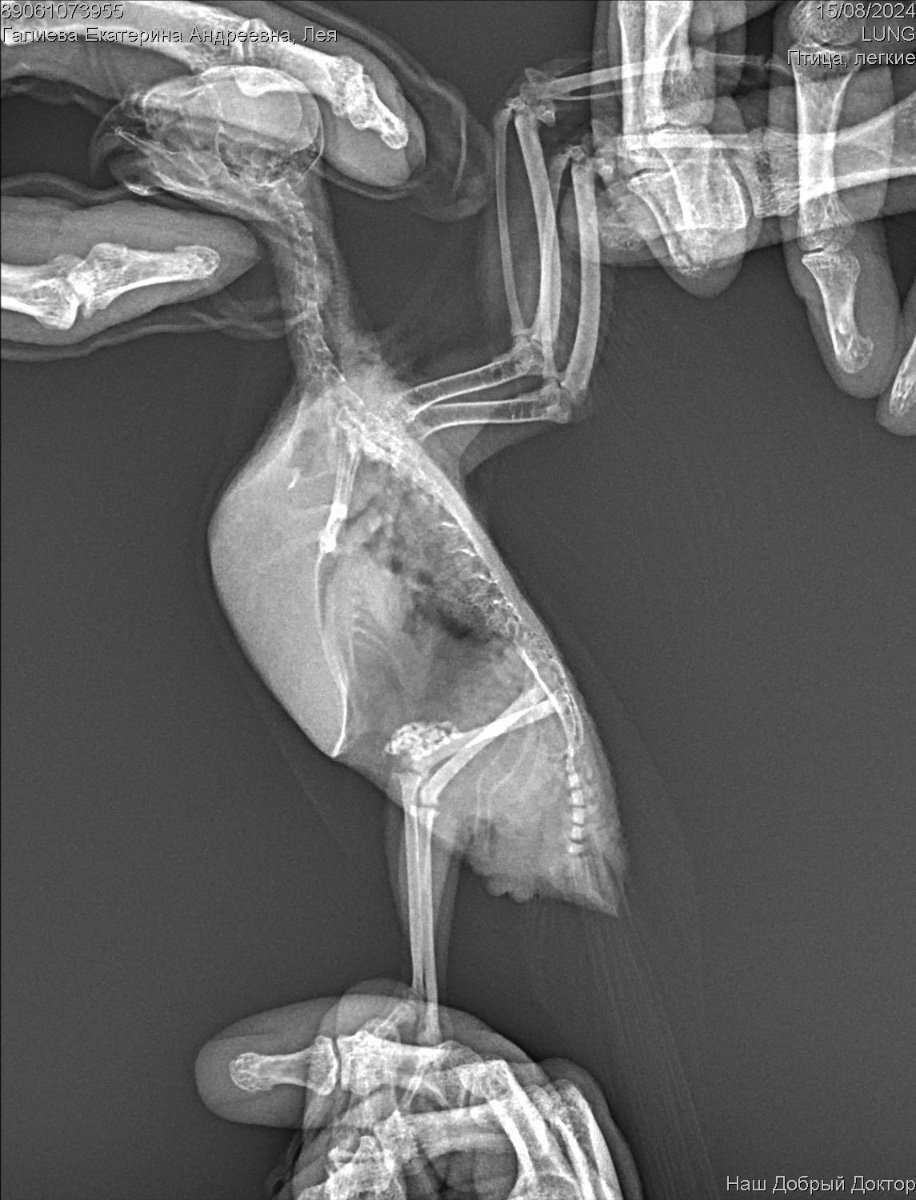

Рекомендован был рентген, по рентгену орнитолог сказала , что к попугая :

Аэросаккулит(воспаление

воздушных мешков), пневмония, нефрит, гепатомегалия, повышенная плотность костей связана с гиперестрогенизмом

Если здесь есть орнитологи, прошу помогите пожалуйста, я была на консультации 3 врачей, я боюсь давать своей птичке Амоксиклав и тербинафин целый месяц. Не много ли это ? Как вы считаете ? И пожалуйста посмотрите рентген умоляю, скажи , что вы видите ? Насколько плохой анализ помета ? И насколько серьезны поставленные диагнозы? И возможно ли это вылечить?  Остальные анализы как придут, я приложу фотографии.